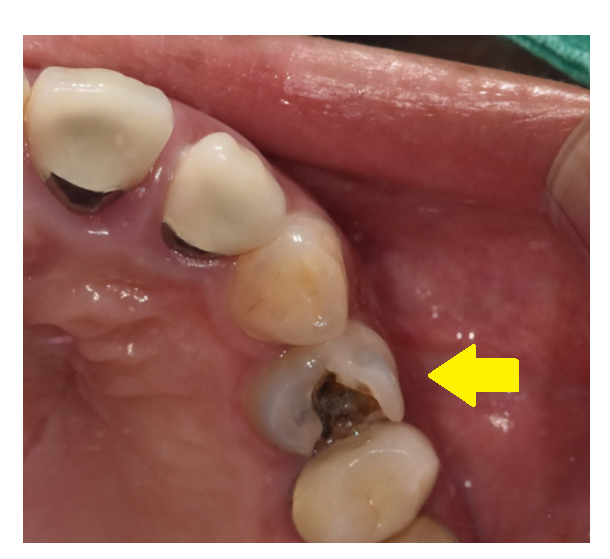

241227 치료한 주변으로 충치가 또 생겼어요.

일반적으로는 충치 부위가 클 수록

파내는 범위 역시 넓고 깊기 때문에 시림이 발생할 확률이 높습니다.

특히나 치아 신경과 가까운 충치일수록 말이죠